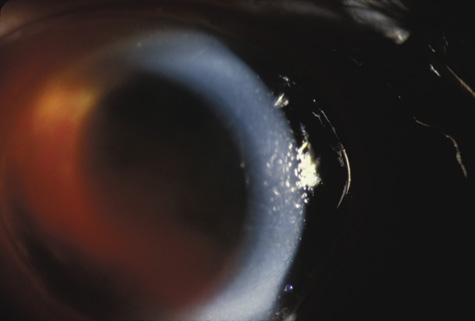

When the cornea is abruptly forced backward by severe blunt trauma, it presses the iris against the lens, preventing the escape of aqueous into the posterior chamber. If enough force is applied, the entrapped aqueous dissects into the ciliary body, resulting in a recessed angle (Fig. 4). This tearing of the ciliary body is responsible for approximately 90% of the hyphemas seen after blunt trauma.31,32 Other causes of hemorrhage include separation of the iris from the ciliary body (iridodialysis) and sphincter tears. Ultrasound biomicroscopy can be useful in diagnosing dissection of the ciliary body or iridodialysis (Fig. 5).33–35

Fig. 5. Ultrasound biomicroscopy image of cyclodialysis (arrow). “C” identifies the cornea, “S” identifies the sclera.